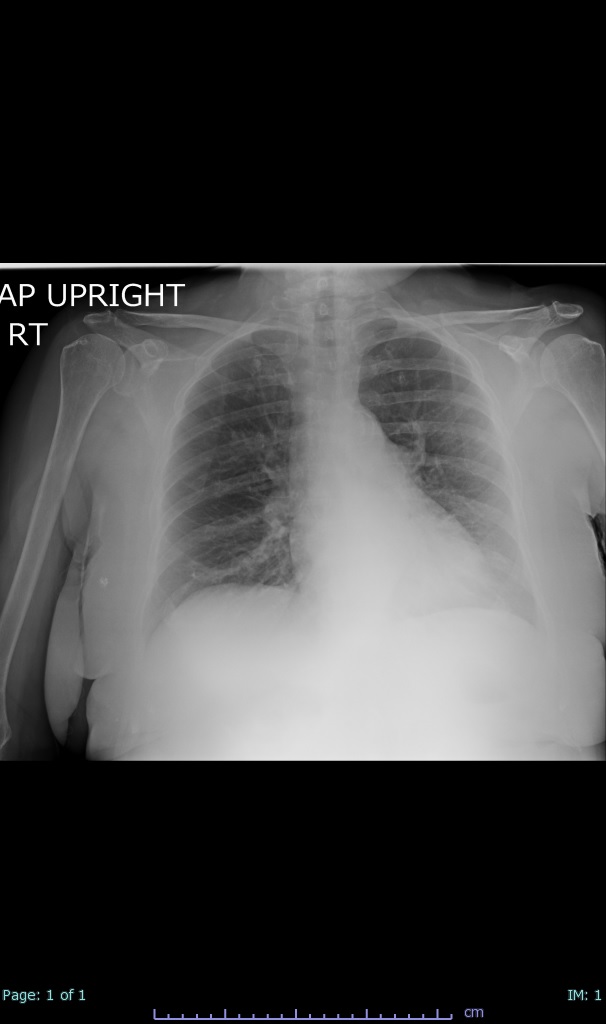

- 66% had some + CXR finding I could correlate to a CT finding

- 100% subpleural involvement, 33% + centrolobular involvement

- 40% even apical/basilar, 27% basilar dom, 5% mid dom. 1/17